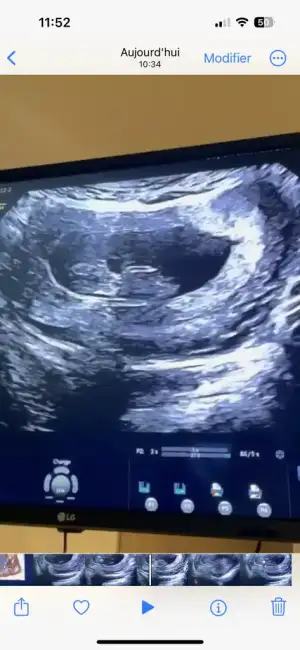

Kızlar sabahtan sırtım ağrıyor tutulmuştur diye önemsemedim şimdi lavaboya gittim pembe kırmızı gibi az bı kan geldi ne yapmalıyım korkudan ölecem

Sana bu mesajı yazdıktan bi kaç saat sonra baya kahverengi akıntım oldu yatayım dinleneyim dedim geçer ama pembe kırmızıya döndü hemen acile gittim. Bebekte kesede bi sorun yoktu çok şükür kalp atışı vs herşey normaldi. Progestan başladım ve dinlenmeye çalışıyorum. Doktor sebebini söylemiş miydi ? Senin de 8. Haftalardı sanırım yanlış hatırlamıyorsam.Bence çok vakit kaybetmeden acile git bir şekilde müdahale edilir ya da varsa bi sorun tespit edilir. En azından için rahat eder.